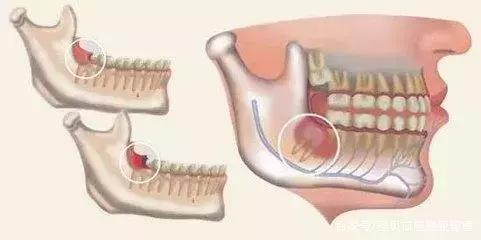

1.由于人类食物的变化而带来咀嚼器官的退化,下颌骨有逐渐缩小的现象,因而造成牙列与颌骨不协调,智齿萌生的位置不足,成为智齿阻生的原因。

3.临床上智齿部分萌出,也是伴发智齿冠周炎的直接原因。智齿在萌生过程中,冠部往往被牙龈瓣覆盖,与牙冠之间形成较深的盲袋,食物及细菌极易嵌塞于盲袋内,一般很难通过漱口和刷牙被清理干净;加之口腔内有非常适宜的温度和湿度,致成为细菌繁殖的温床。

1、 由于萌出不全,后侧的牙龈覆盖,其部分牙冠形成冠周袋积存食物和细菌,可以造成局部软组织经常发炎,疼痛难忍,甚至导致张口受限而进食困难。

4、 会影响其他牙齿龋坏:阻生智齿能使第二磨牙龋坏。向前倾斜的智齿,其牙冠顶在前牙的颈部,这两颗牙之间形成一个滞留区,由于食物残渣的滞留,得不到正常清洁,细菌繁殖产酸,腐蚀牙齿,造成第二磨牙牙颈容易发生龋齿,往往就诊时已不能保留,需要拔除。